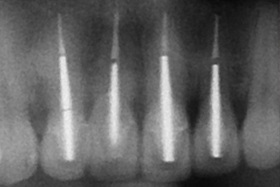

舊牙冠拆除後,舊牙冠拆除後,術後X光片。

治療後,X光片。